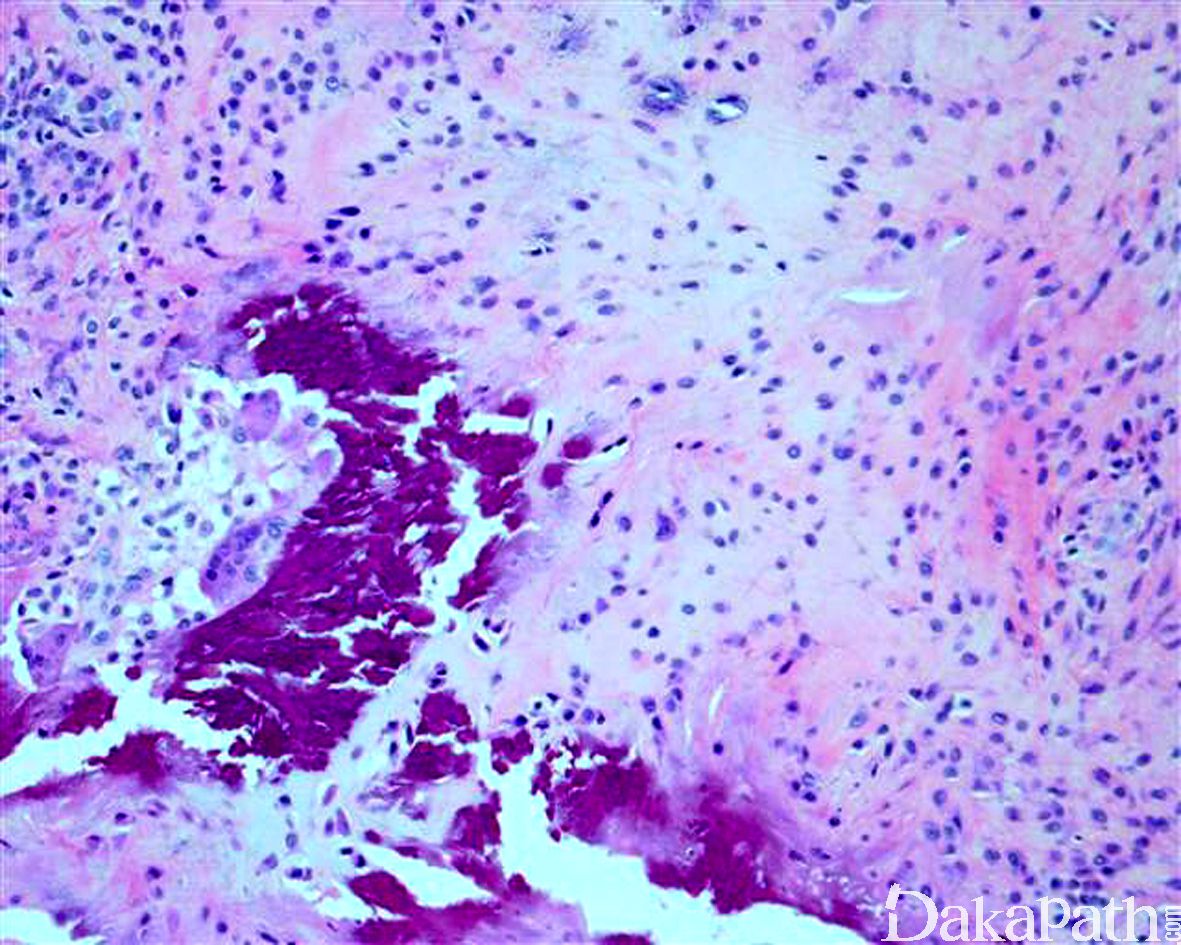

- 由胖梭形细胞栅栏状围绕软骨或点状钙化灶周围为其特征性改变;部分病例表现为梭形纤维母细胞浸 润性生长,细胞之间可见丰富的胶原纤维,两种结构可同时存在;

- 在钙化灶周围有时可见散在的破骨样多核巨细胞。